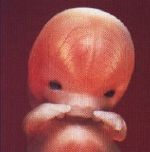

Wenn Föten lebensfähig werden

Das künftige Leben existiert schon vor dem Embryo in Form von Spermien und Eizellen. Der Embryo ist nur eine Weiterentwicklung, er ist eine potenzielle Person. Die Würde, die man ihm zuschreibt, ist meiner Meinung nach progressiv. Zum Beispiel gibt es kein Begräbnis für eine Fehlgeburt. Das französische Recht ist da sehr klar: Die Grenze ist die 22. Schwangerschaftswoche. Davor wird der Fötus nicht als Person ins Geburtenregister eingetragen. Das zeigt, das Leben wird in seinen verschiedenen Stadien durchaus unterschiedlich bewertet. Nach der 22. Woche ist der Fötus lebensfähig, wenn ihm medizinisch geholfen wird. Davor sind die Organe nicht hinreichend entwickelt. Das ist ein grundsätzlicher Unterschied."

Prof. Dr. René Frydman, Gynäkologe in Paris, Berater des französischen Forschungsministerium - unter anderem in Fragen der Bioethik